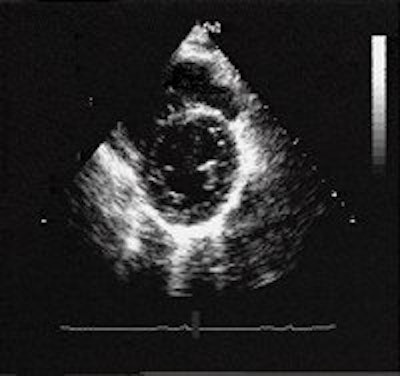

![]() |

| HCM is the most common cause of sudden cardiac death in young athletes and people younger than 30 years of age. In a normal heart, the heart walls are 11 mm or less in thickness (above and below). |